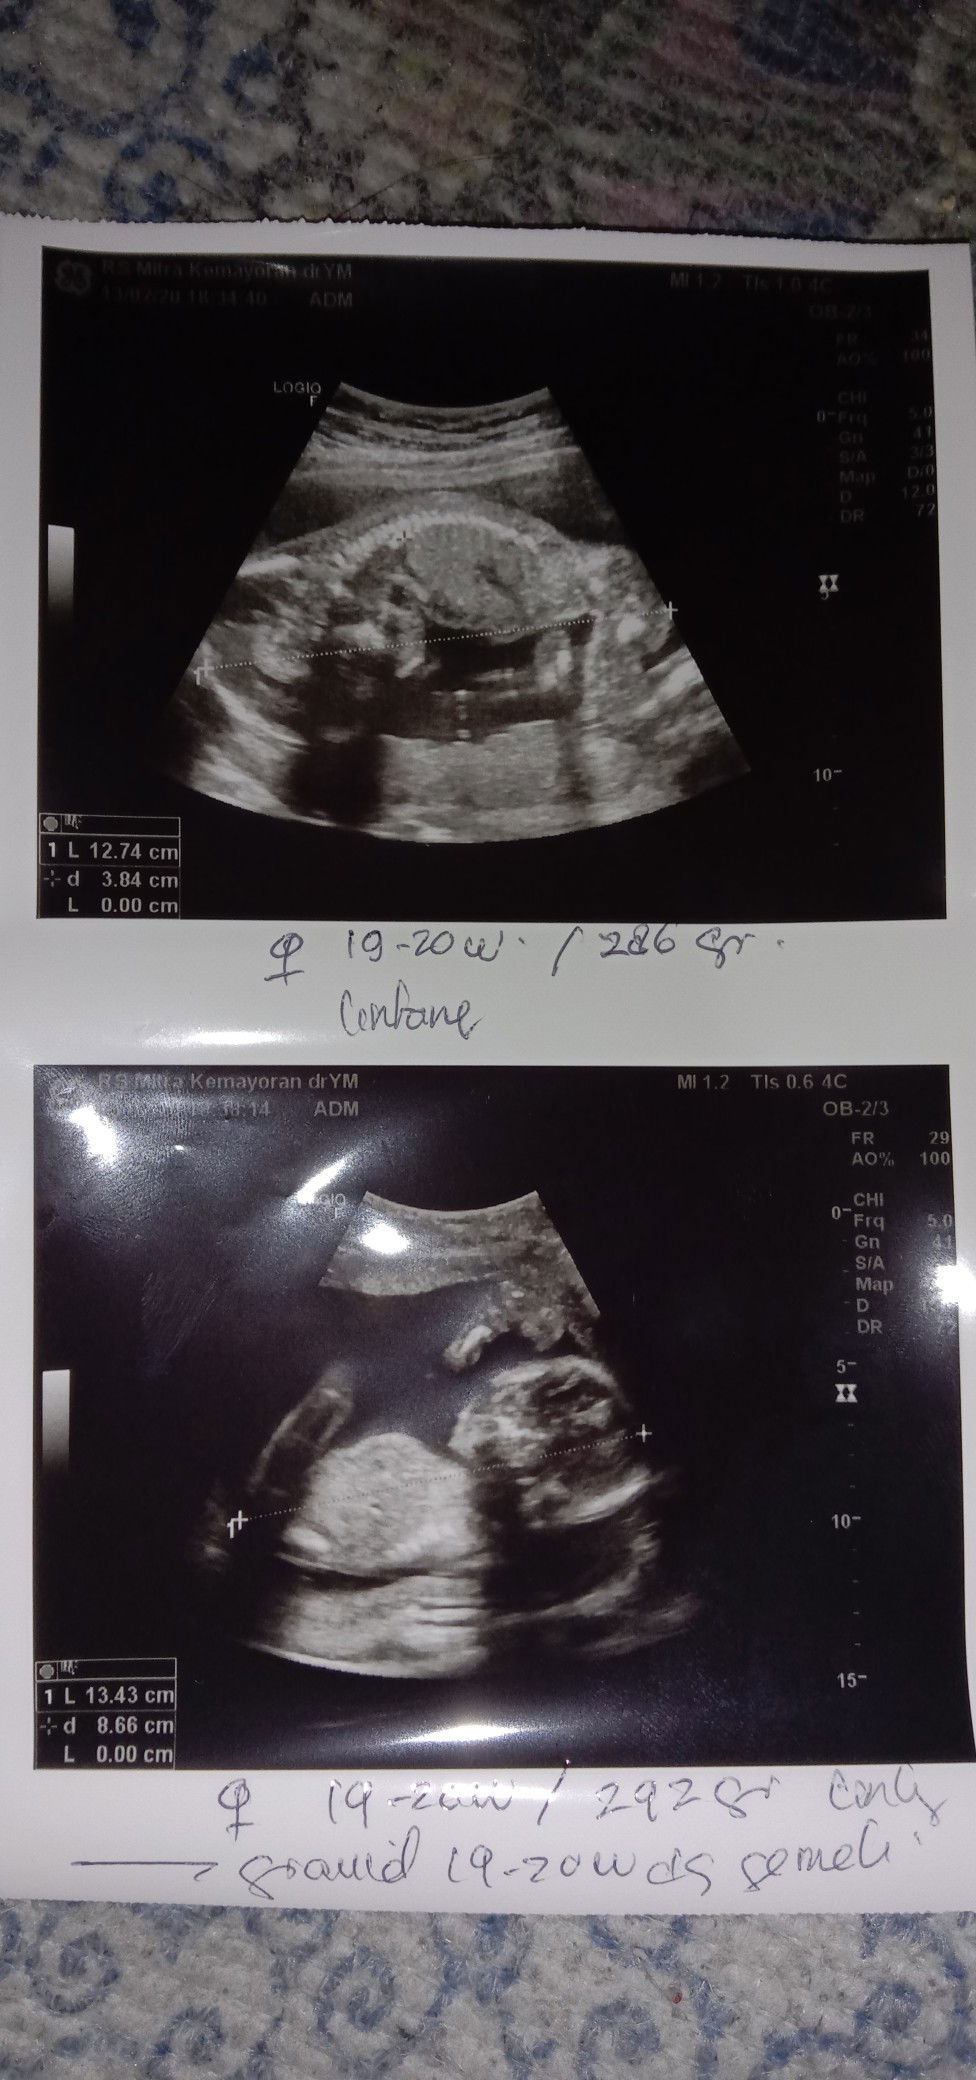

Baby twins

Alhamdulillah, baby twins nya pada sehat hehe dan dua" nya perempuan karna mereka 1 kantong gada sekat nya dan kembar identik. Alhamdulillah bgt yaallah, sehat trus ya de diperut mommy. Dan ini udh 15weeks❤